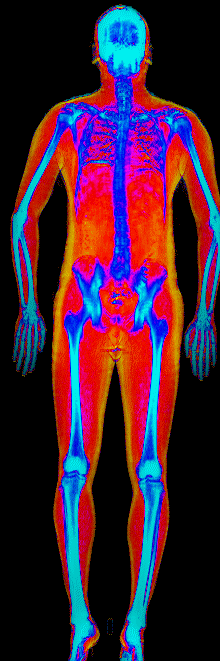

What Muscle Gain Looks Like on a DEXA Scan

Gained 21.7 lb lean · 158 → 184 lb · Age 31

Gained 12.1 lb lean, lost 9.2 lb fat · 188 → 191 lb · Age 27

Gained 9.2 lb lean, lost 6.6 lb fat · 173 → 176 lb · Age 33